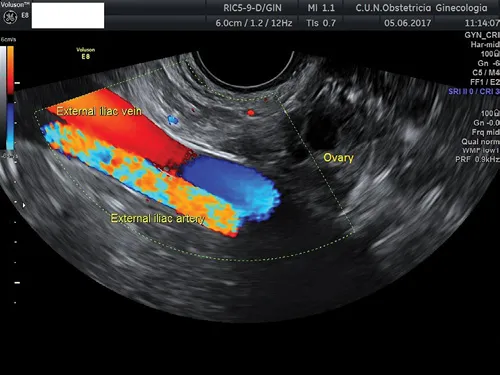

External iliac vessels are easily identified running parallel to the pelvic wall (Figure 1.1). The vein is larger than the artery and is located over the artery. The latter is clearly seen beating in virtually all women. It is important to insonate the vessels parallel to them in order to obtain a sagittal view of the vessels. This can be achieved by moving the endovaginal probe laterally and anteriorly.

Figure 1.1 Transvaginal ultrasound showing right external iliac vessels. The ovary is seen lying over these vessels.